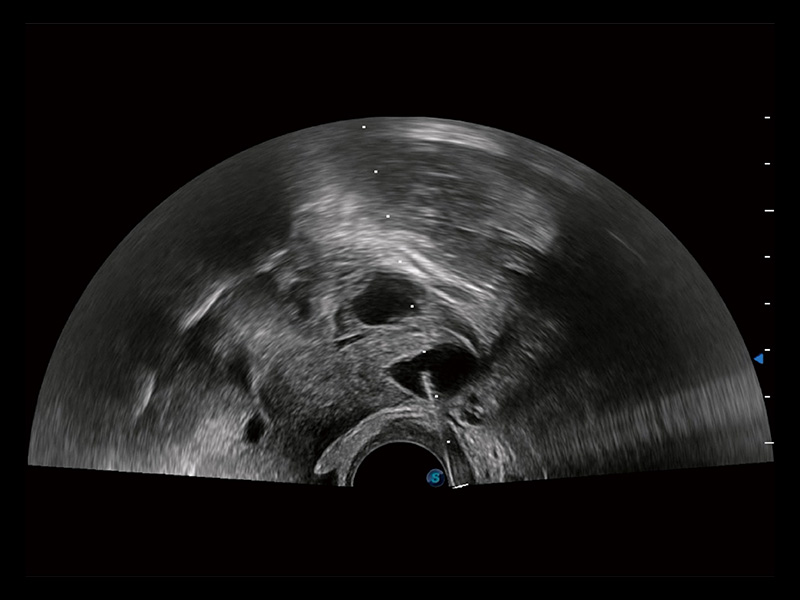

“生育问题”即关系民族复兴,也关系亿万家庭的幸福。随着婚育年龄推迟、社会压力增加等因素,越来越多人群也面临着“生不出、生不好”的问题。辅助生殖作为治疗不孕不育最有效的方法之一,也逐渐成为育儿新希望。而超声检查能为生殖需求人群的初诊评估提供宝贵的信息。 P20 Elite是哈哈体育官网匠心打造的一款生殖应用型彩超。她继承哈哈体育官网高端极光平台,突破性地将多款新型芯片及硬件模块进行整合,均衡了高端系统性能与小巧灵动机身。P20 Elite卓越的图像质量搭载专科探头,旨在为您提供全面的辅助生殖解决方案。

P20 Elite配备了丰富的生殖探头群和临床应用功能,在卵泡监测、穿刺取卵、胚胎移植、妊娠确认等领域,为生殖需求人群提供了新的临床机会,重新定义高端超声如何应用于生殖健康检查。